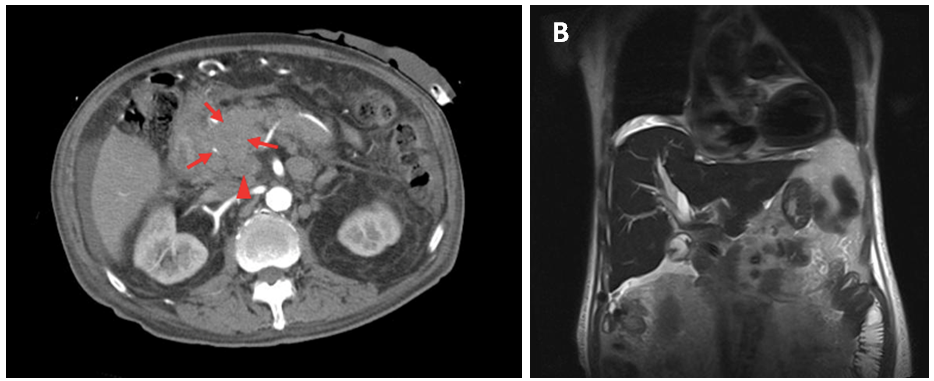

Figure 1 1A: Contrast-enhanced CT scan: a hypodense heterogeneous poorly-defined mass of the head of pancreas (arrows) and retroperitoneal and mesenteric lymph nodes (arrowhead). Scarce peri-hepatic ascites. 1B: MR cholangiography: Moderate intra and extrahepatic bile duct dilatation.